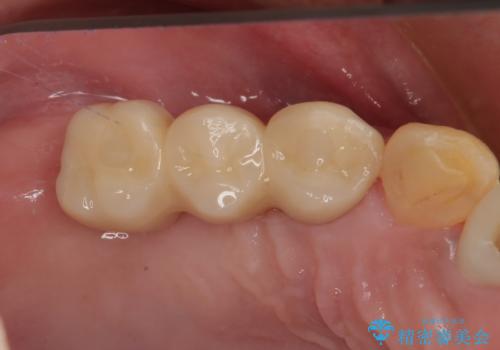

抜歯即時埋入インプラントによる補綴治療の特徴は、短期間であることや処置数が少ないことが挙げられます。また、表側の歯肉の陥凹を避けることができるというメリットがあります。しかしながら、今回は歯根破折の程度が酷く、やや膨らみを失うこととなりましたが、スムーズに治療を終えることができました。

臼歯部は前歯以上に炎症が酷く、抜歯即時埋入不可と判断されましたが、従来法よりは短期間で終えることができました。